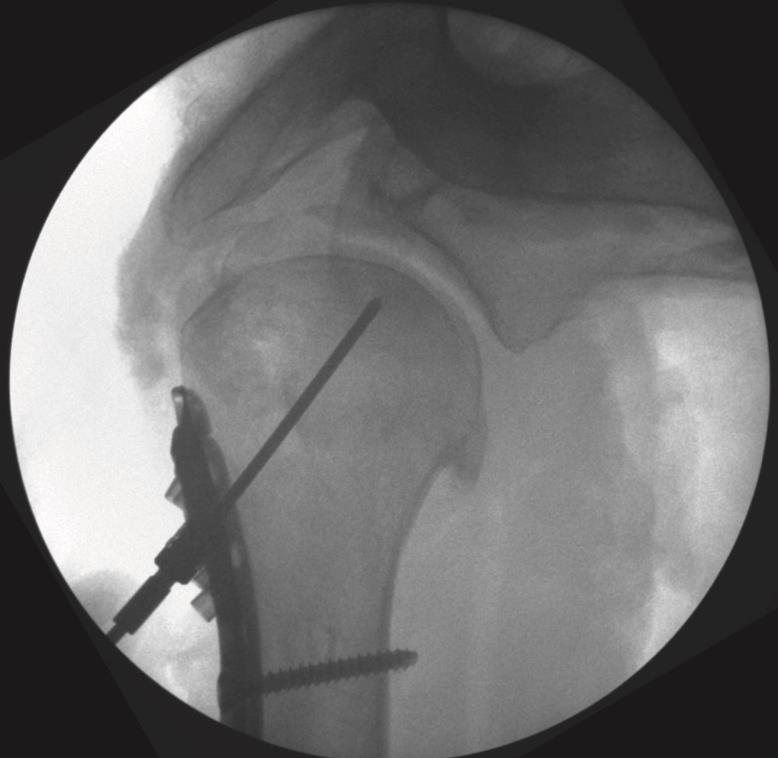

• Provisional plate fixation and central K-wire

• A threaded K-wire guide is placed into the central post of the plate, and a 2.4 mm K-wire is drilled toward the center of the humeral head.

• Fluoroscopy in AP and lateral views is used to verify that the wire is center–center and follows the desired 135 degree trajectory.

• If the K-wire is off-center, it is removed, plate position is adjusted, and the wire is re-drilled until the central position is satisfactory.

• Central peg preparation and insertion

• The central K-wire and its guide are removed.

• A 6.0 mm drill is used under power to perforate the near cortex through a central PDG.

• A 6.0 mm blunt safe-tip drill attached to a handle is then advanced manually to the subchondral region, again stopping short of the joint surface under fluoroscopic control.

• Length is measured from the drill scale, and the PDG is removed using the central peg driver.

• An appropriately sized 6.0 mm smooth locking central peg is inserted and locked into the plate with the T-10 driver to provide a strong central column.

• Final fluoroscopy confirms reduction, peg and screw lengths, plate height relative to the greater tuberosity, and absence of joint penetration or subacromial impingement risk.